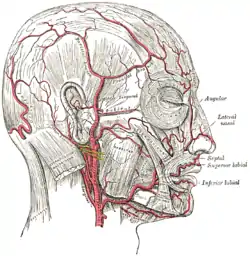

| The arteries of the face and scalp | |

Giant cell arteritis (GCA), also called temporal arteritis, is an inflammatory autoimmune disease of large blood vessels.[4][7] Symptoms may include headache, pain over the temples, flu-like symptoms, double vision, and difficulty opening the mouth.[3] Complication can include blockage of the artery to the eye with resulting blindness, as well as aortic dissection, and aortic aneurysm.[4] GCA is frequently associated with polymyalgia rheumatica.[4]

The cause is unknown.[2] The underlying mechanism involves inflammation of the small blood vessels that supply the walls of larger arteries.[4] This mainly affects arteries around the head and neck, though some in the chest may also be affected.[4][8] Diagnosis is suspected based on symptoms, blood tests, and medical imaging, and confirmed by biopsy of the temporal artery.[4] However, in about 10% of people the temporal artery is normal.[4]